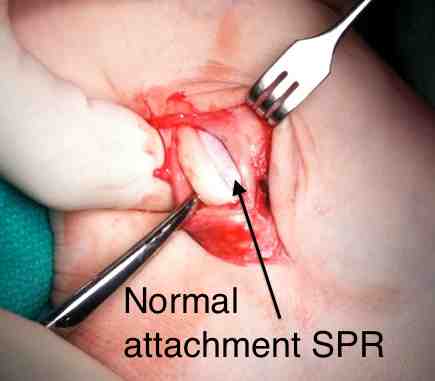

Direct repair of SPR +/- groove deepening

Technique

Identify SPR pathology

- typically avulsed from fibula

- allows tendons to sublux anteriorly

Identify avulsion of SPR from fibula, assess groove, insert anchors in fibula